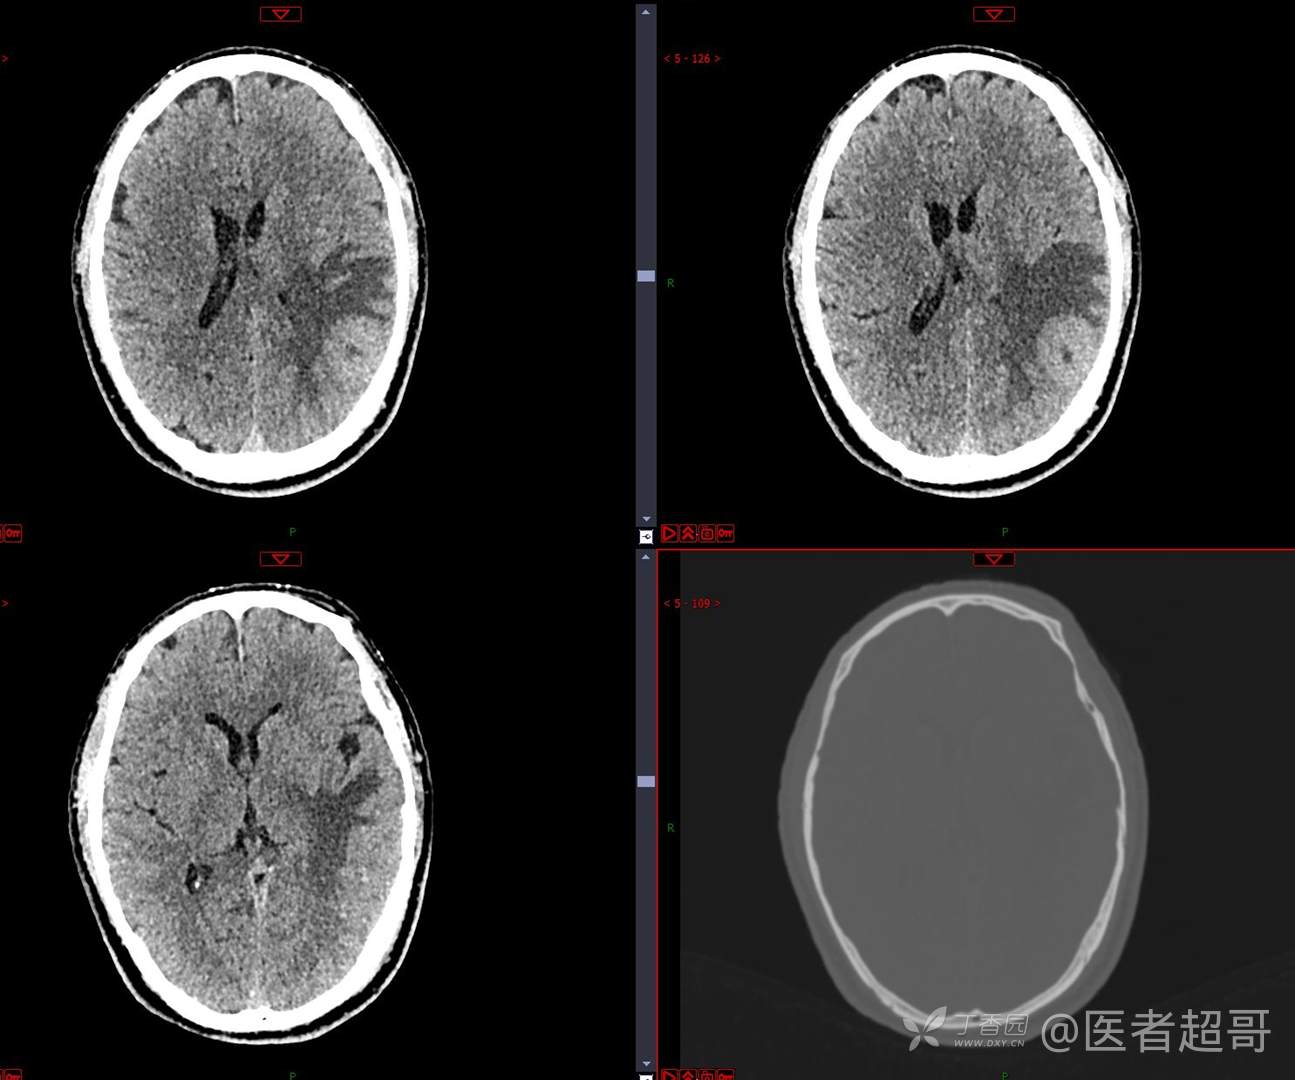

比较典型病例,CT、MRI齐全,请分析,领丁当!

男,56岁

主 诉:查体发现颅内占位10天。

现病史:患者于约10天前于我院查体时行颅脑MRI提示左侧顶叶占位病变,无头痛头晕,无恶心呕杜,无肢体活动不利,无感觉异常,现患者为求进一步治疗,就诊于我科门诊,门诊以“颅内占位性病变”收入我科。患者自发病以来,神志清,精神可,饮食及睡眠差,大小便无明显异常,体重无明显变化。